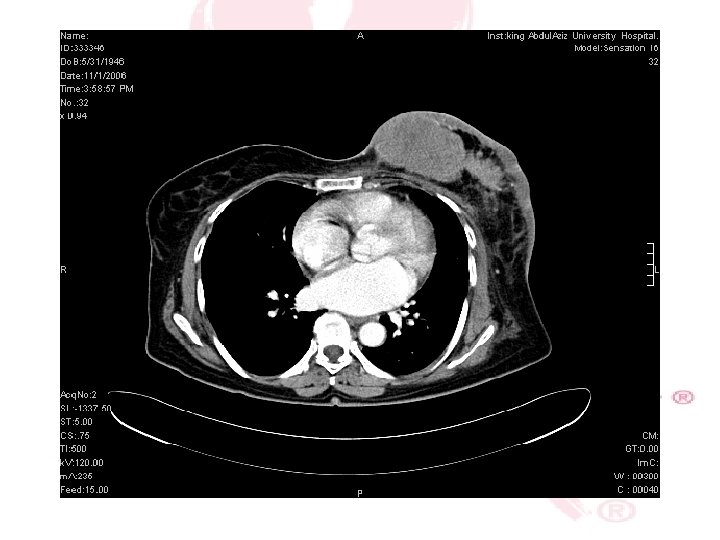

CT SCAN CHEST , ABDOMEN &PELVIS